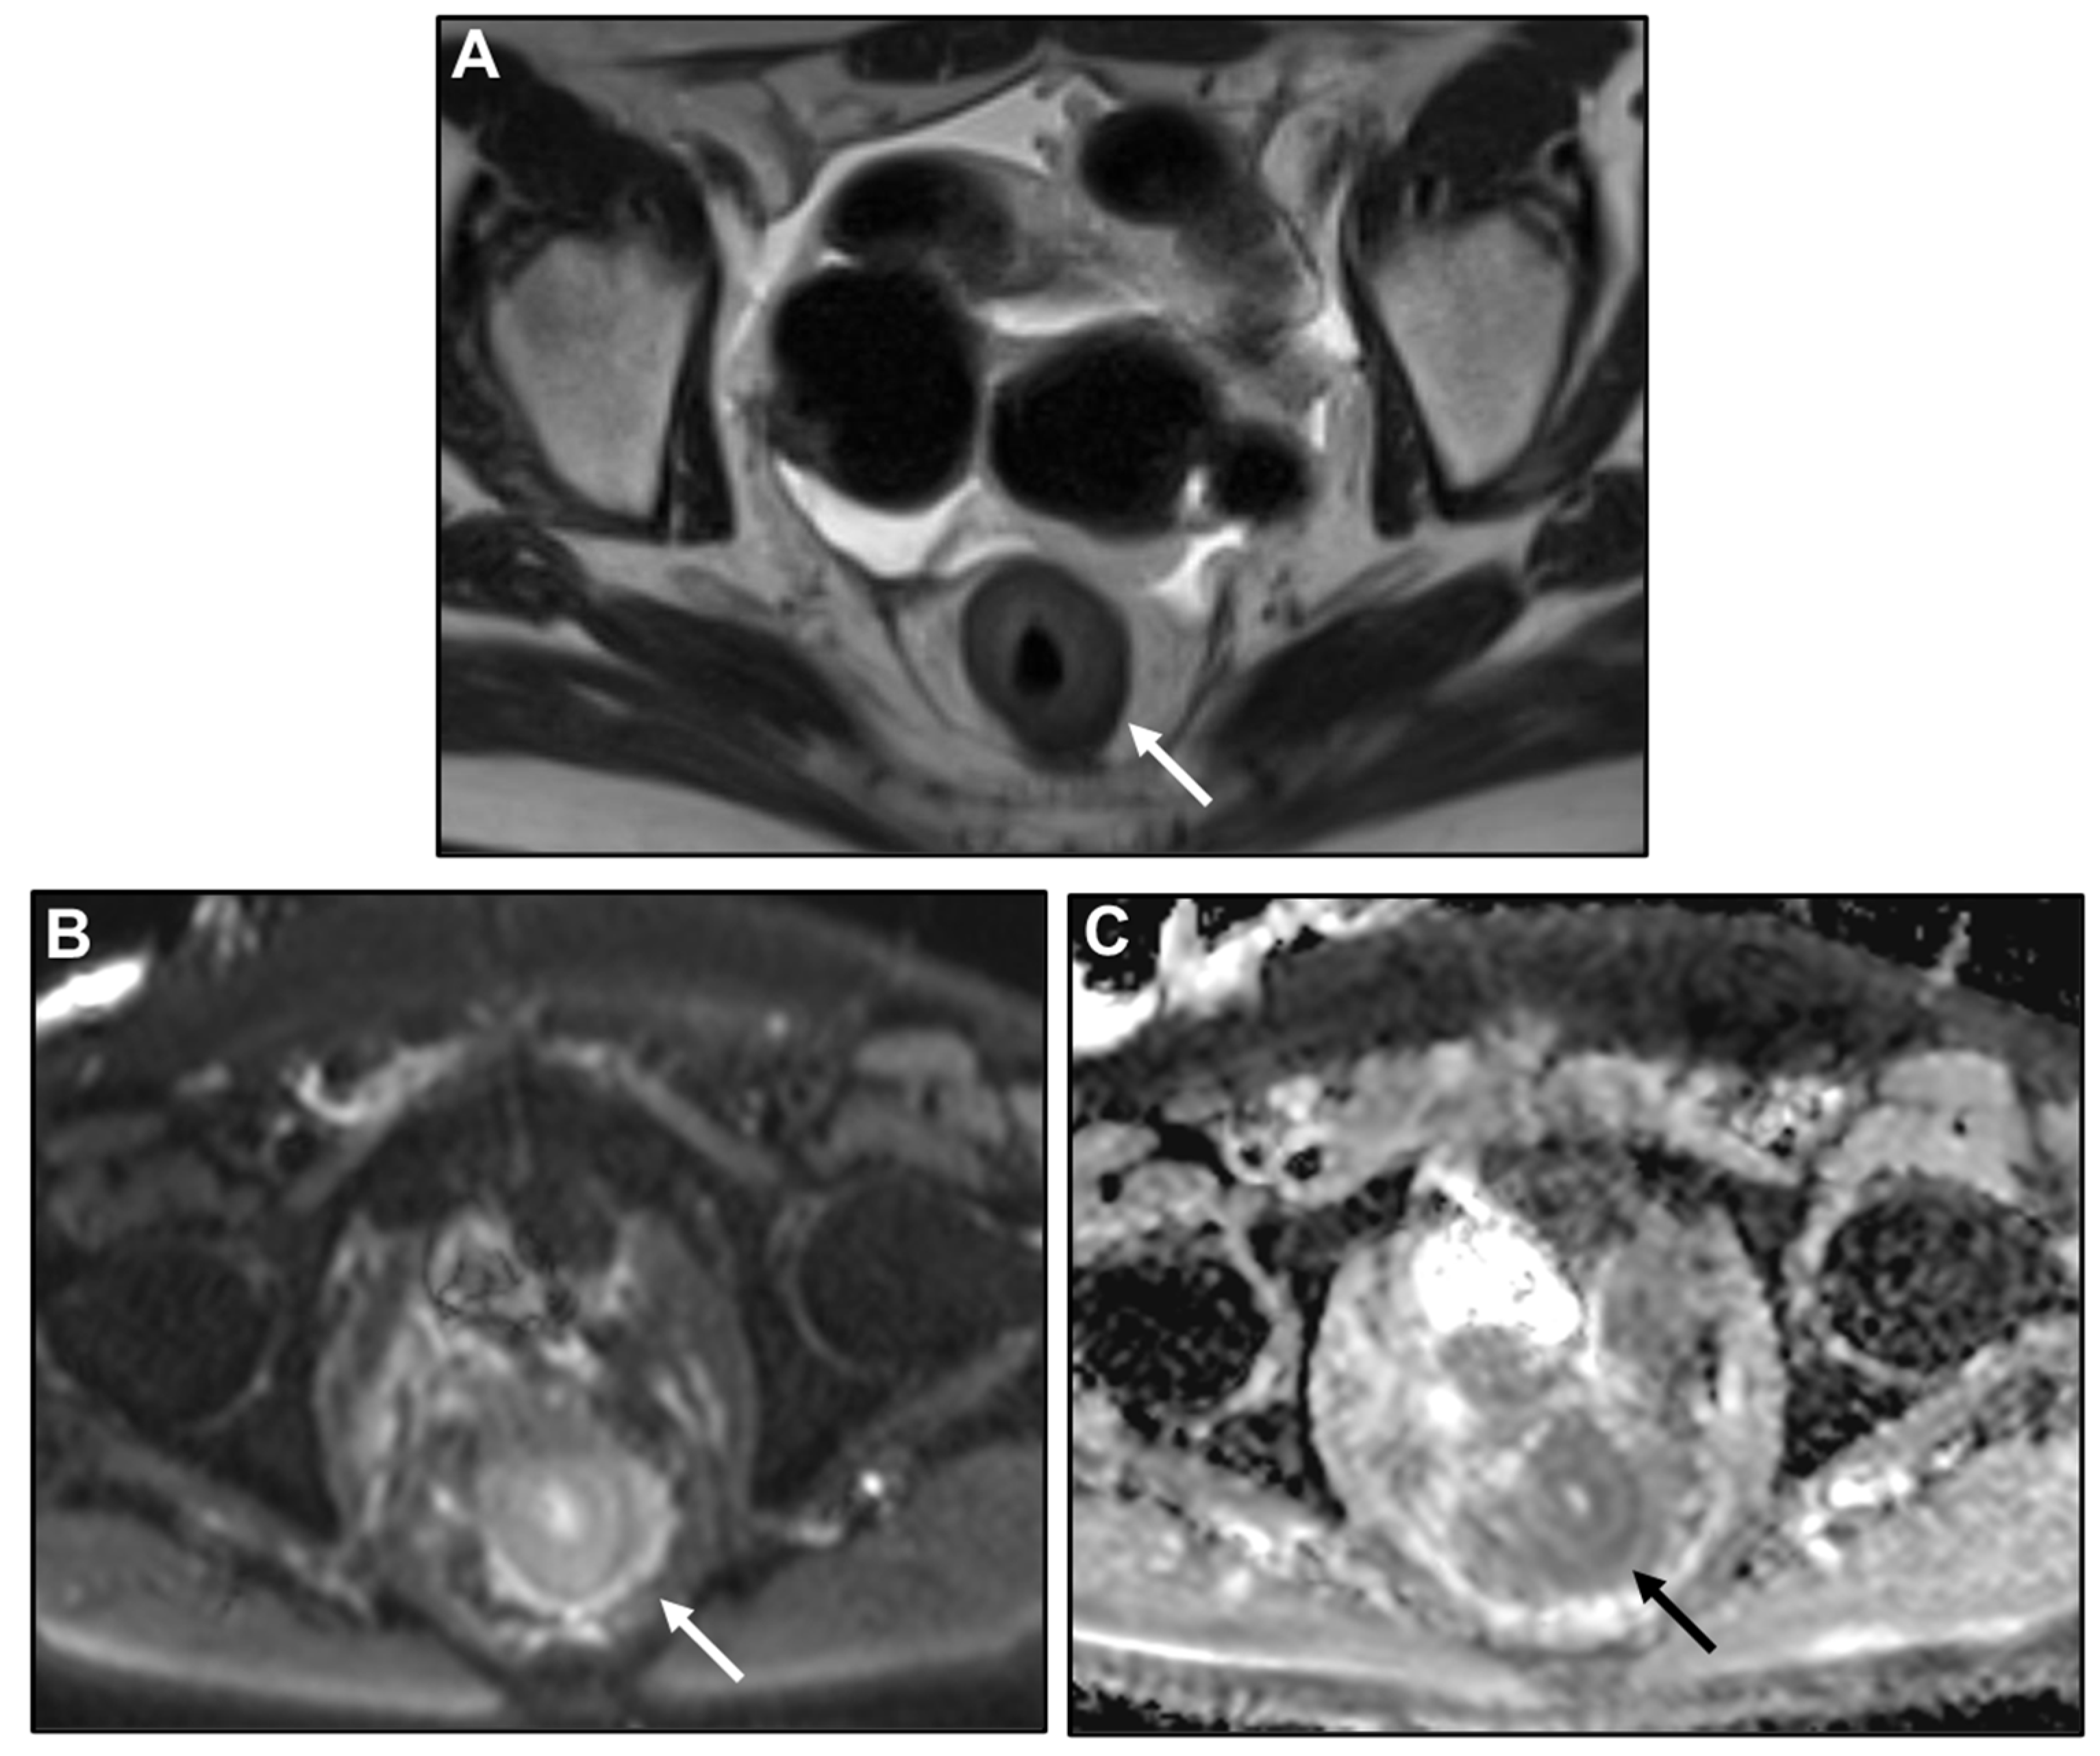

Presacral Fat Tissue and Rectovaginal Septum Infiltration and T2-Weighted Imaging (T2WI) Hypointense Extramural Tumour Component